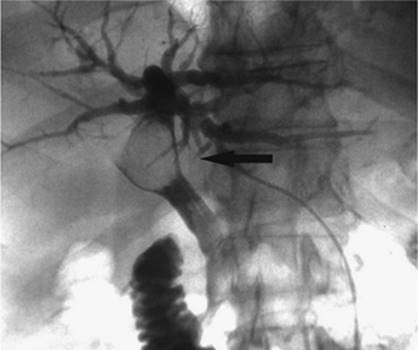

000431

Figure 35.14. Failed endoscopic placement of common bile duct (CBD) stent due to the presence of a large mass (black arrow) within the CBD. (Image courtesy of James Caridi, MD.)

Figure 35.16. Patient presents with biliary obstruction. On hospital day 1, external drainage has been achieved using a right-sided bile duct approach. Cholangiogram shows complete obstruction in the mid common bile duct (CBD) (black arrow).